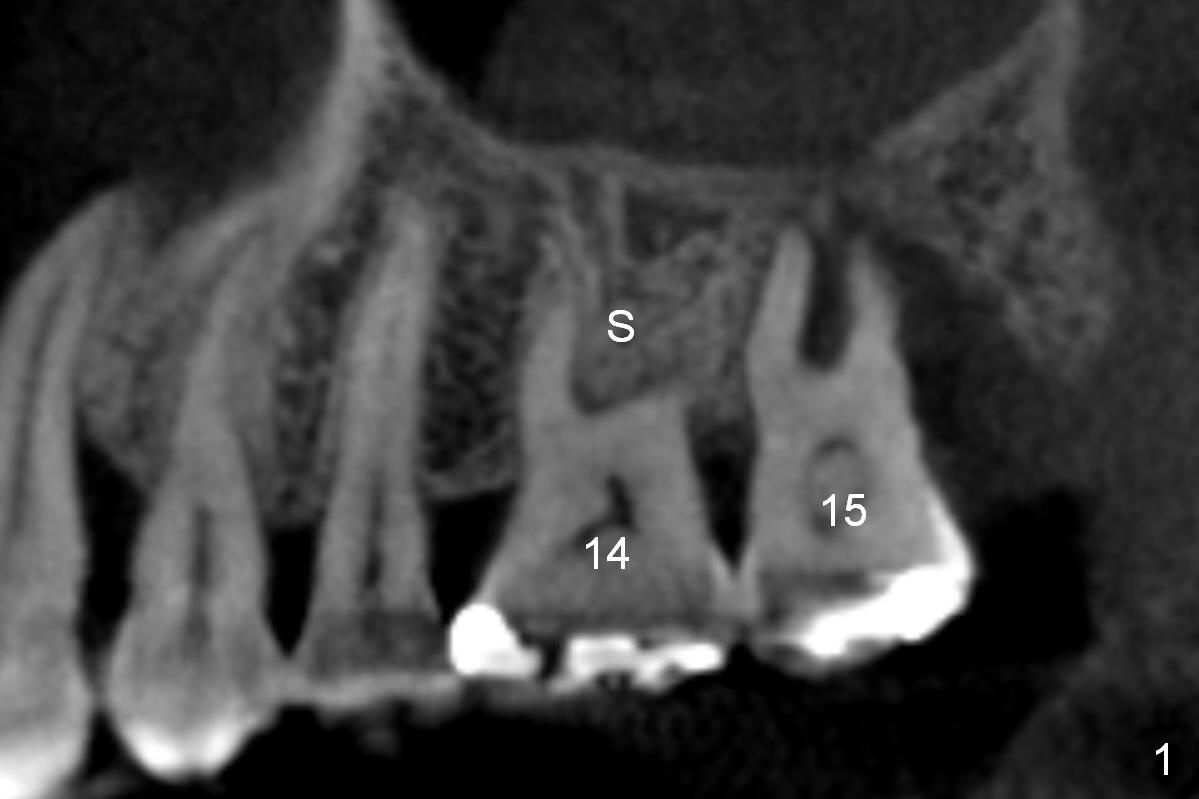

It is noteworthy that the tooth #14 was less affected than #15 22 months earlier (Fig.1 (CBCT sagittal section), 2 (axial), 3 (coronal)). Calculus on the surface of the palatal root (Fig.6 P) is associated with the palatal abscess (Fig.5 P). S: septum.